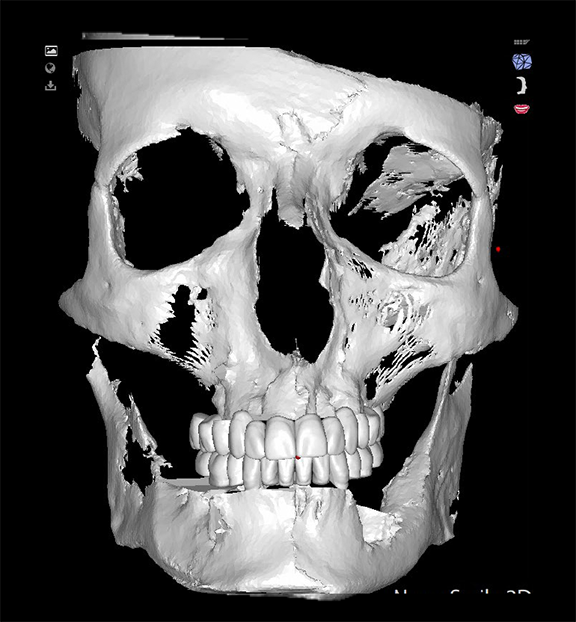

Going from virtual to reality, topographical landmarks on the bony surfaces are used as 3D blueprints for implant planning. Every bit of information needed is on the screen (Figure 14) and is verified, allowing rendering of a surgical result with a degree of precision not possible with computer-based planning. Regardless of how complicated the implant planning, the practitioner can concentrate on the oral cavity with the computer screen providing the reference points.2-4

Fig 14. Topographical landmarks on the bony surfaces are used as 3D blueprints for implant planning.

Figure 14